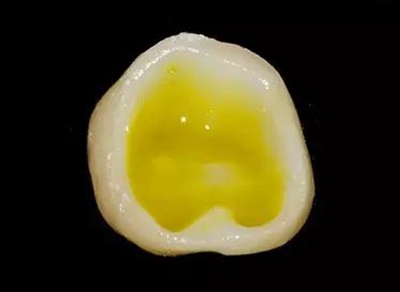

牙体制备完成后的牙合面观

牙合面观察牙体预备之后的情况。

轴壁按要求预留0.8 mm 宽度。